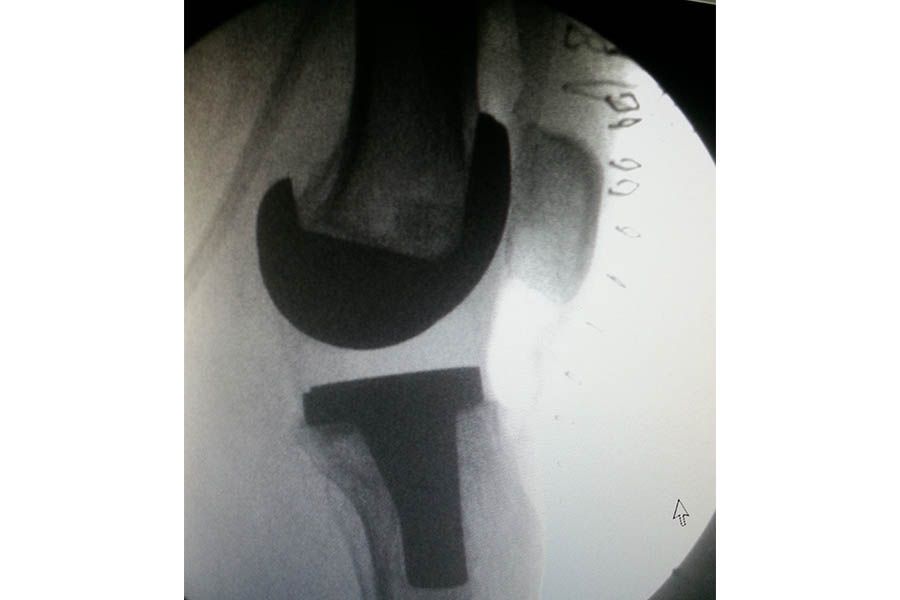

Total Knee Replacement

Case 1